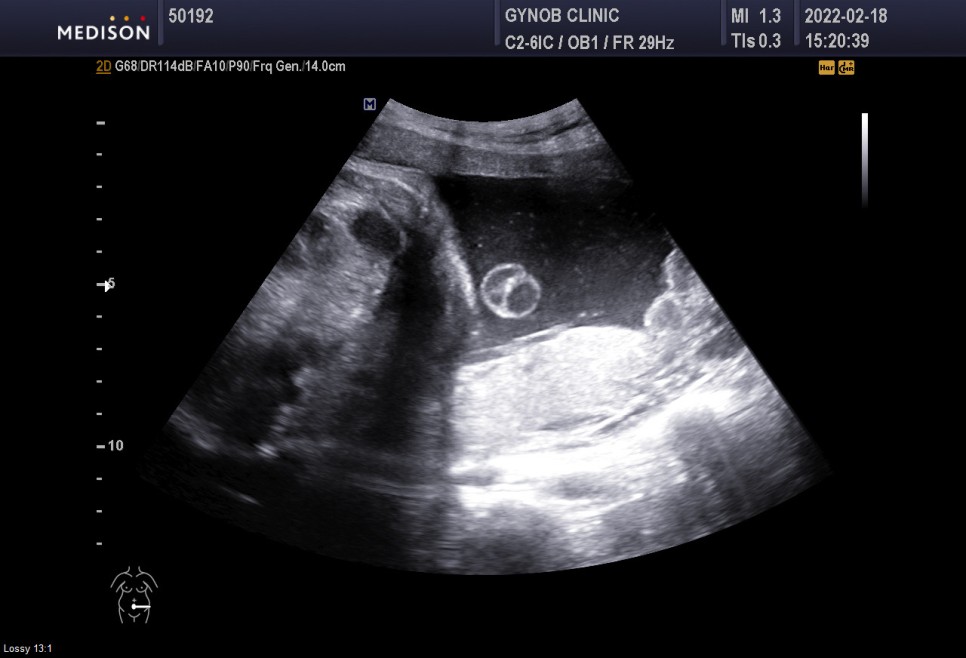

▲초음파실에서 초음파도 봤다=심상덕 원장님은 초음파를 5분 동안 꼬박꼬박 챙겨보신다.

아기의 머리 위치는 정상*경부 제대륜 1회 신경 쓸 필요는 없습니다.

- 경부 탯줄은 탯줄이 아기의 목 부분을 감고 있다는 것을 의미한다

경부제 대륜 1번 탯줄에 목을 1번 감고 있다는 뜻이다.너무 신경 안 써도 될 것 같아